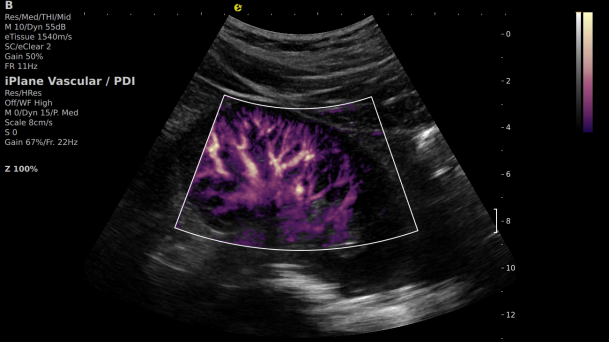

在肾移植领域,医生最怕的不是手术刀下的惊心动魄,而是那些手术后肉眼看不见的危机——急性排斥反应导致的血小板聚集形成的微血栓、毛细血管网损伤等...这些“隐形杀手”曾让无数移植肾在悄无声息中衰竭。而hjc888黄金城官网医疗(ESI)的iPlane Vascular平面波超微细血流显像技术,正是为破解这一难题而生。

这项革命性技术通过三大创新实现质的飞跃:

1) 基于OmniSound?平面波超快速平台,超声信号采集帧频提高了200倍(25000Hz)。

2) 可检测20-50μm级细小血管低速血流信号,能看清头发丝1/2粗细的微血管;

3) 通过血管指数(VI)定量评估局部血管密度,以定量化数据实时监测血流灌注情况,预判肾功能恢复情况;

超微视血流显像显示肾脏五级血管

从术前评估到术中到术后,再到终身监护,当20-50μm级的超微血流信号在屏幕上跳动,我们看到的不仅是技术的精进,更是生命的律动。iPlane Vascular正在重新定义肾移植监护的标准——让医生拥有了"显微视力",让每一个微小血管的异常都无所遁形,让每一次免疫排斥的萌芽都被及时扼制。